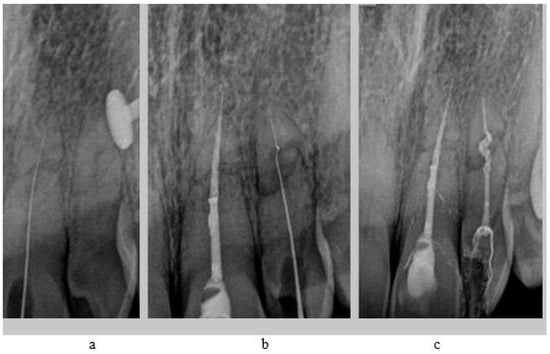

In tooth 21, we successfully performed the root canal treatment with minimal loss of tooth tissue, covering both fragments of the fractured tooth root. The aim of the study is to assess whether the treatment of tooth 22 with root canal obliteration using endodontic navigation will bring positive clinical and radiological effects. The use of the endodontic template will be evaluated through clinical and radiological assessments of the tooth before the initiation of endodontic treatment and after the completion of the treatment. After obtaining both written and verbal consent to perform the endodontic procedure, an endodontic template was designed. The patient presented for root canal treatment of tooth 22. During the initial visit, a CBCT (Carestream 9300C, Carestream Dental, 2016, Atlanta, GA, USA) of the maxillary arch was completed (Figure 3a), and an intraoral scan (Carestream 3600) of the jaw was performed.

Figure 3. CBCT images presenting tooth no. 22: (a) before treatment, (b) after treatment.